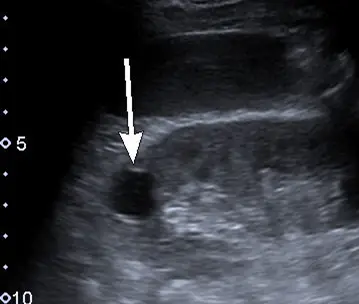

附圖為腎臟超音波影像,箭號所指最可能為何?

附圖為一張灰階腎臟超音波(renal ultrasound)影像。圖中箭號所指處位於腎實質(renal parenchyma)內,呈現出以下三個非常典型的超音波特徵:

- 無回音(Anechoic):病灶內部呈現全黑,沒有任何內部回音(internal echoes),代表其內容物為清澈液體。

- 邊緣平滑且界線清楚(Smooth and well-defined borders):病灶的壁極薄且規則,與周圍正常腎臟組織分界明顯。

- 後方回音增強(Posterior acoustic enhancement):病灶正後方的組織亮度明顯高於周遭同深度的組織。這是因為音波穿透囊腫內液體時的衰減(attenuation)遠小於穿透周遭實質組織,導致探頭接收到後方傳回的訊號相對較強。

- (A) renal cyst:影像中「無回音、邊緣平滑、後方回音增強」為單純性腎囊腫(simple renal cyst)的標準三大超音波診斷要件,與圖中箭號所指特徵完全吻合。